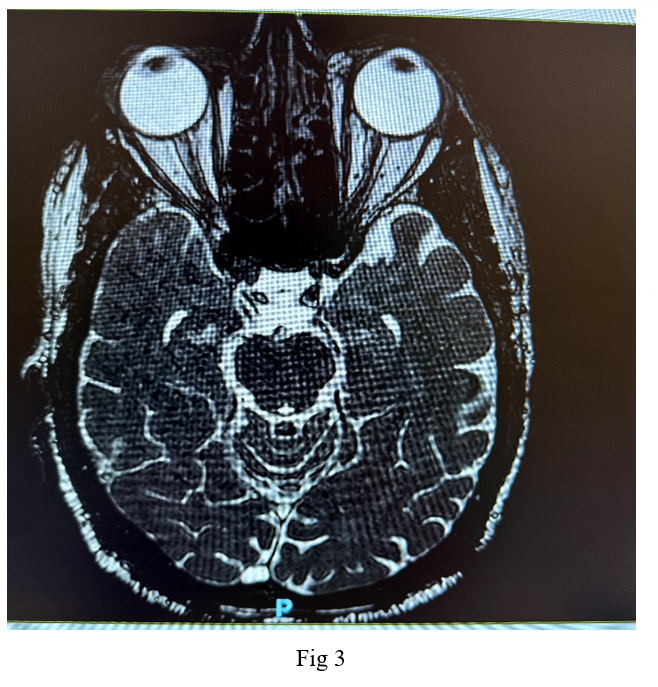

Imaging studies, including a native CT scan of the brain, MRI of the brain, and MRI of the orbit without contrast, revealed no pathological findings. Additionally, laboratory tests, including a complete blood count, erythrocyte sedimentation rate, C-reactive protein, fasting blood sugar, glycated hemoglobin, thyroid function tests, kidney function tests, B12 levels, blood glucose, and blood pressure, were all within normal ranges. Following a neurological consultation, he was diagnosed with cluster headache associated with oculomotor nerve palsy.

Neuroimaging, such as Cranial MRI, is essential to rule out structural abnormalities, particularly in patients with symptoms resembling other headache types or conditions like pituitary tumors. Distinguishing cluster headaches from other trigeminal autonomic cephalalgias and primary headache disorders is crucial for appropriate management.

Figure 1